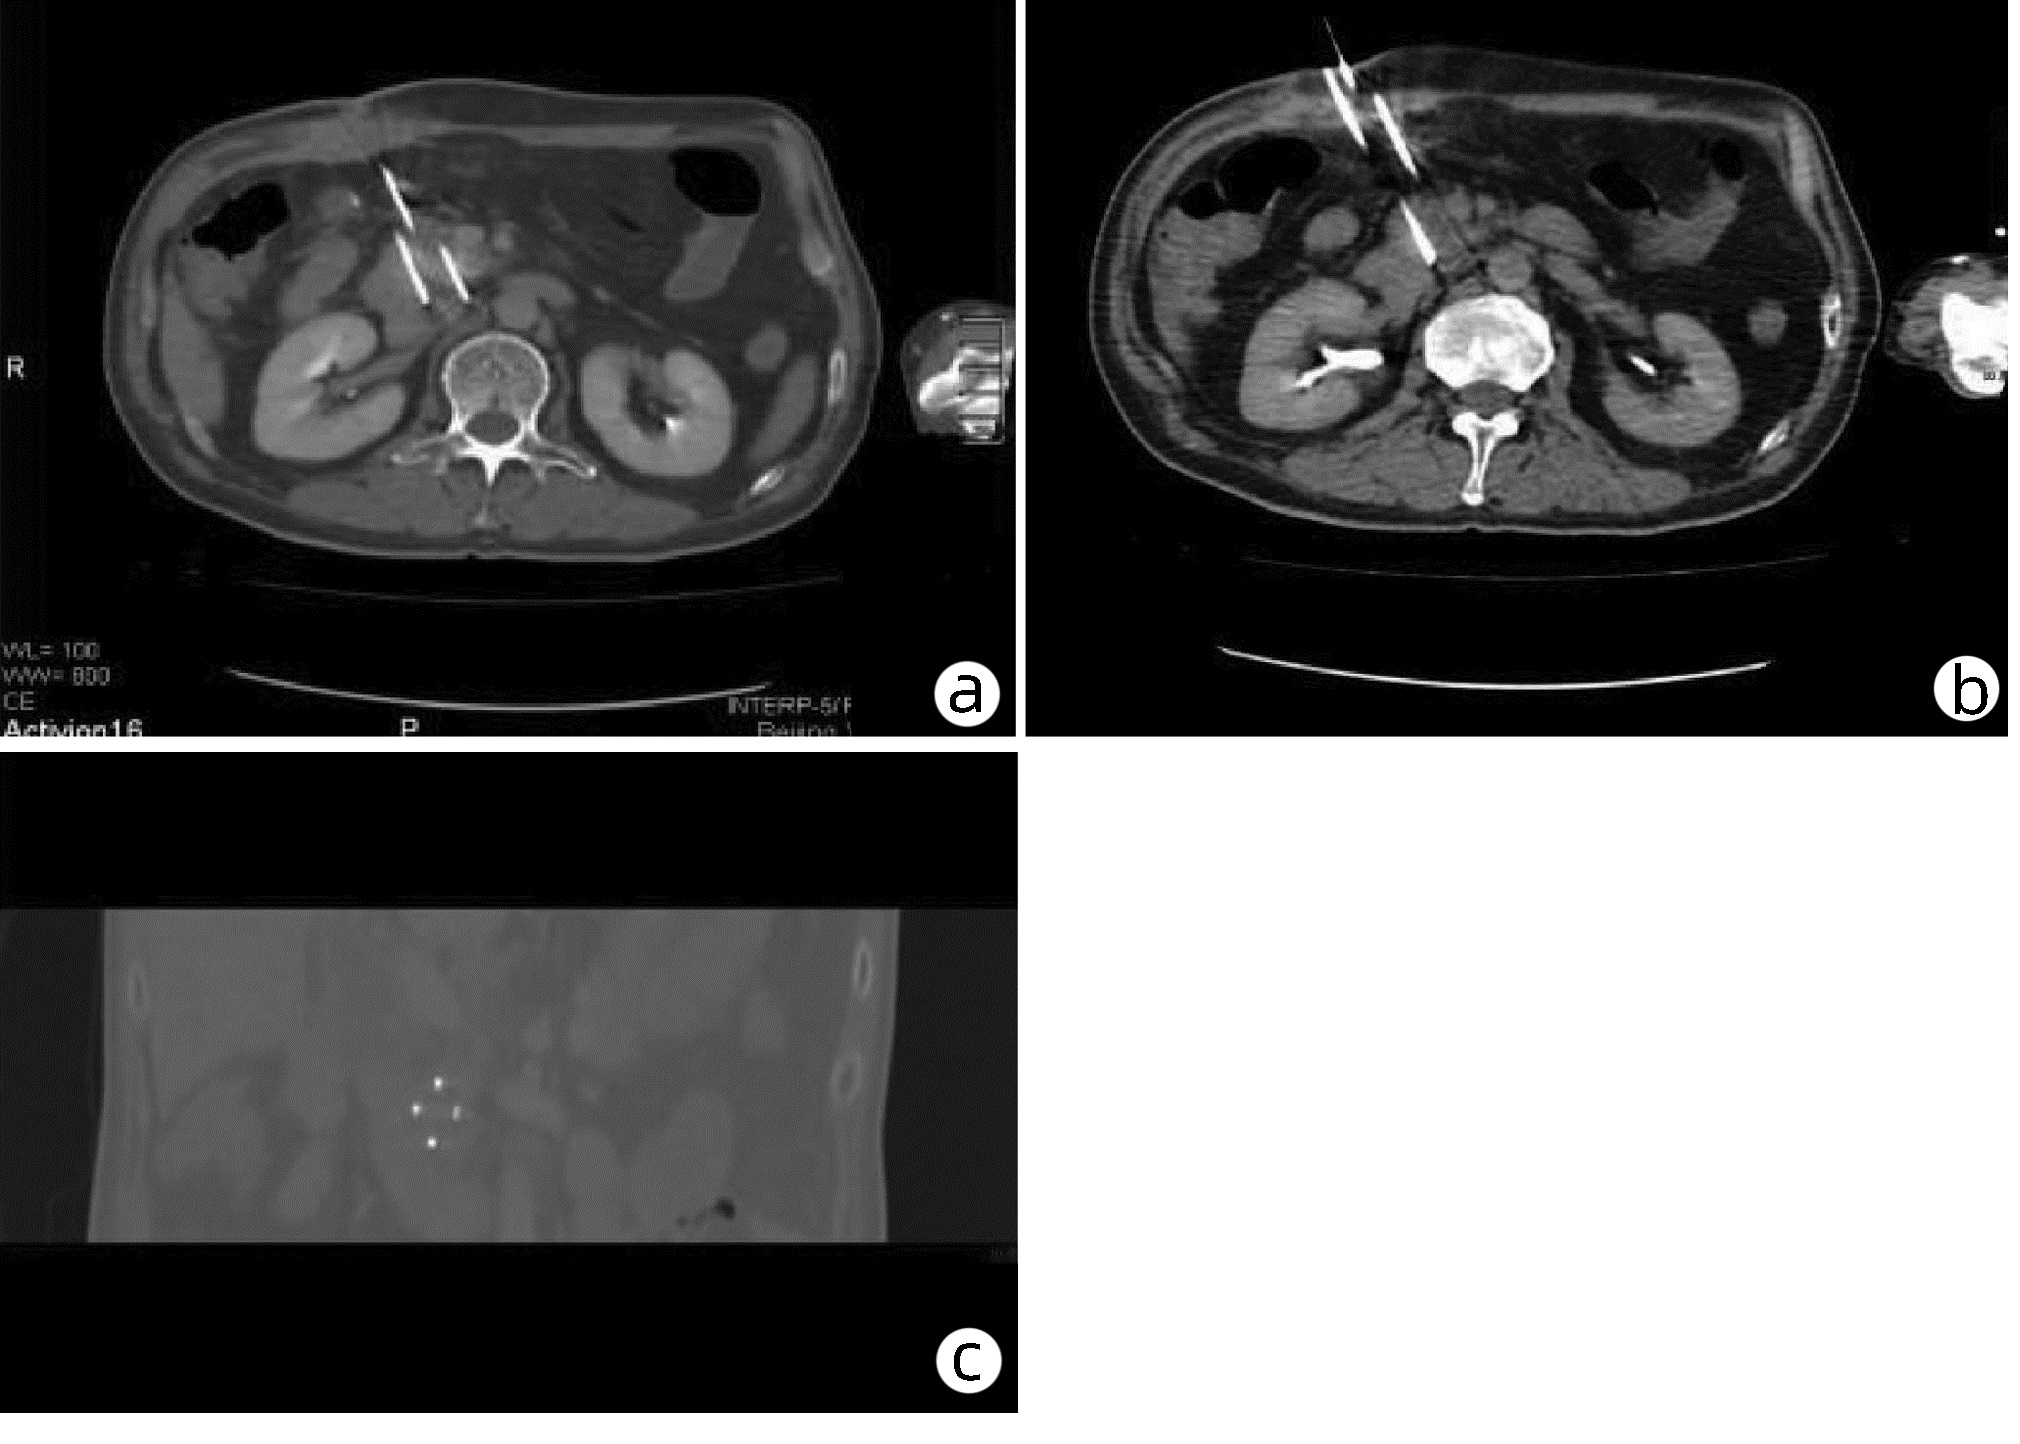

磁共振IDEAL-IQ技术对急性胰腺炎患者脂肪与铁沉积的诊断效能分析

范慧芳, 陈强, 原小军, 罗琳

2022, 38(10): 2320-2324. DOI: 10.3969/j.issn.1001-5256.2022.10.022

摘要(1308) HTML (528) PDF (2190KB)(85)

摘要:

目的  利用IDEAL-IQ技术定量参数脂肪分量(FF)和弛豫率(R2*)对急性胰腺炎(AP)患者胰腺内脂肪沉积和铁沉积进行量化评估,评价其诊断AP的效能。  方法  纳入2020年10月—2021年10月于内蒙古科技大学包头医学院第一附属医院诊治的AP患者72例为AP组,以同期82例健康体检者为对照组。两组研究对象应用GE 3.0T MRI行腹部IDEAL-IQ序列检查,并在MR后处理工作站测量胰腺FF及R2*值。符合正态性分布的计量资料两组间比较采用t检验;不符合正态分布的计量资料两组间比较采用非参数Mann-Whitney U检验。差异有统计学意义的参数进行受试者工作特征曲线分析。以曲线下面积作为评价参数诊断效能的指标。  结果  病例组中FF值显著高于对照组(Z=-10.01,P<0.001),AP组中R2*值高于对照组,差异有统计学意义(Z=-3.73,P<0.001);而轻度与中重度AP间FF和R2*值的差异均无统计学意义(P值均>0.05);FF值和R2*值诊断AP的敏感度分别为100%、48.6%,特异度分别为90.2%、86.6%。  结论  磁共振IDEAL-IQ技术定量参数FF值诊断AP的灵敏度和特异度均较高,是诊断AP的特异性指标,具有很好的临床应用前景。